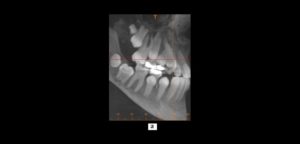

Paciente de sexo masculino de 64 años de edad es referido para evaluación de pieza 3.6 por presentar dolor, el cual ha aumentado en los últimos meses; y solicitan además evaluación ósea en zona de pieza 3.7 para colocación de implante dental.